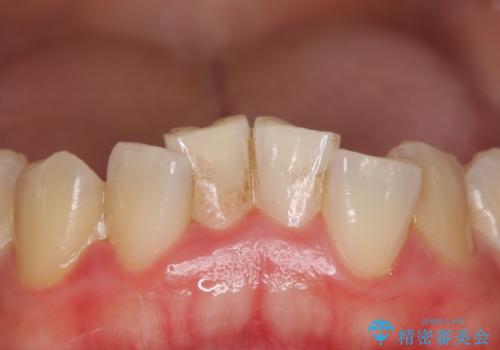

下の前歯に着色(ステイン)が見られたため、処置前クリーニングを行い、着色を除去しました。ホワイトニング後は全体的に白くなりました。ご希望の被せ物の色味になるまでは再度オフィスホワイトニングまたは、ホームホワイトニングの併用をおすすめしました。